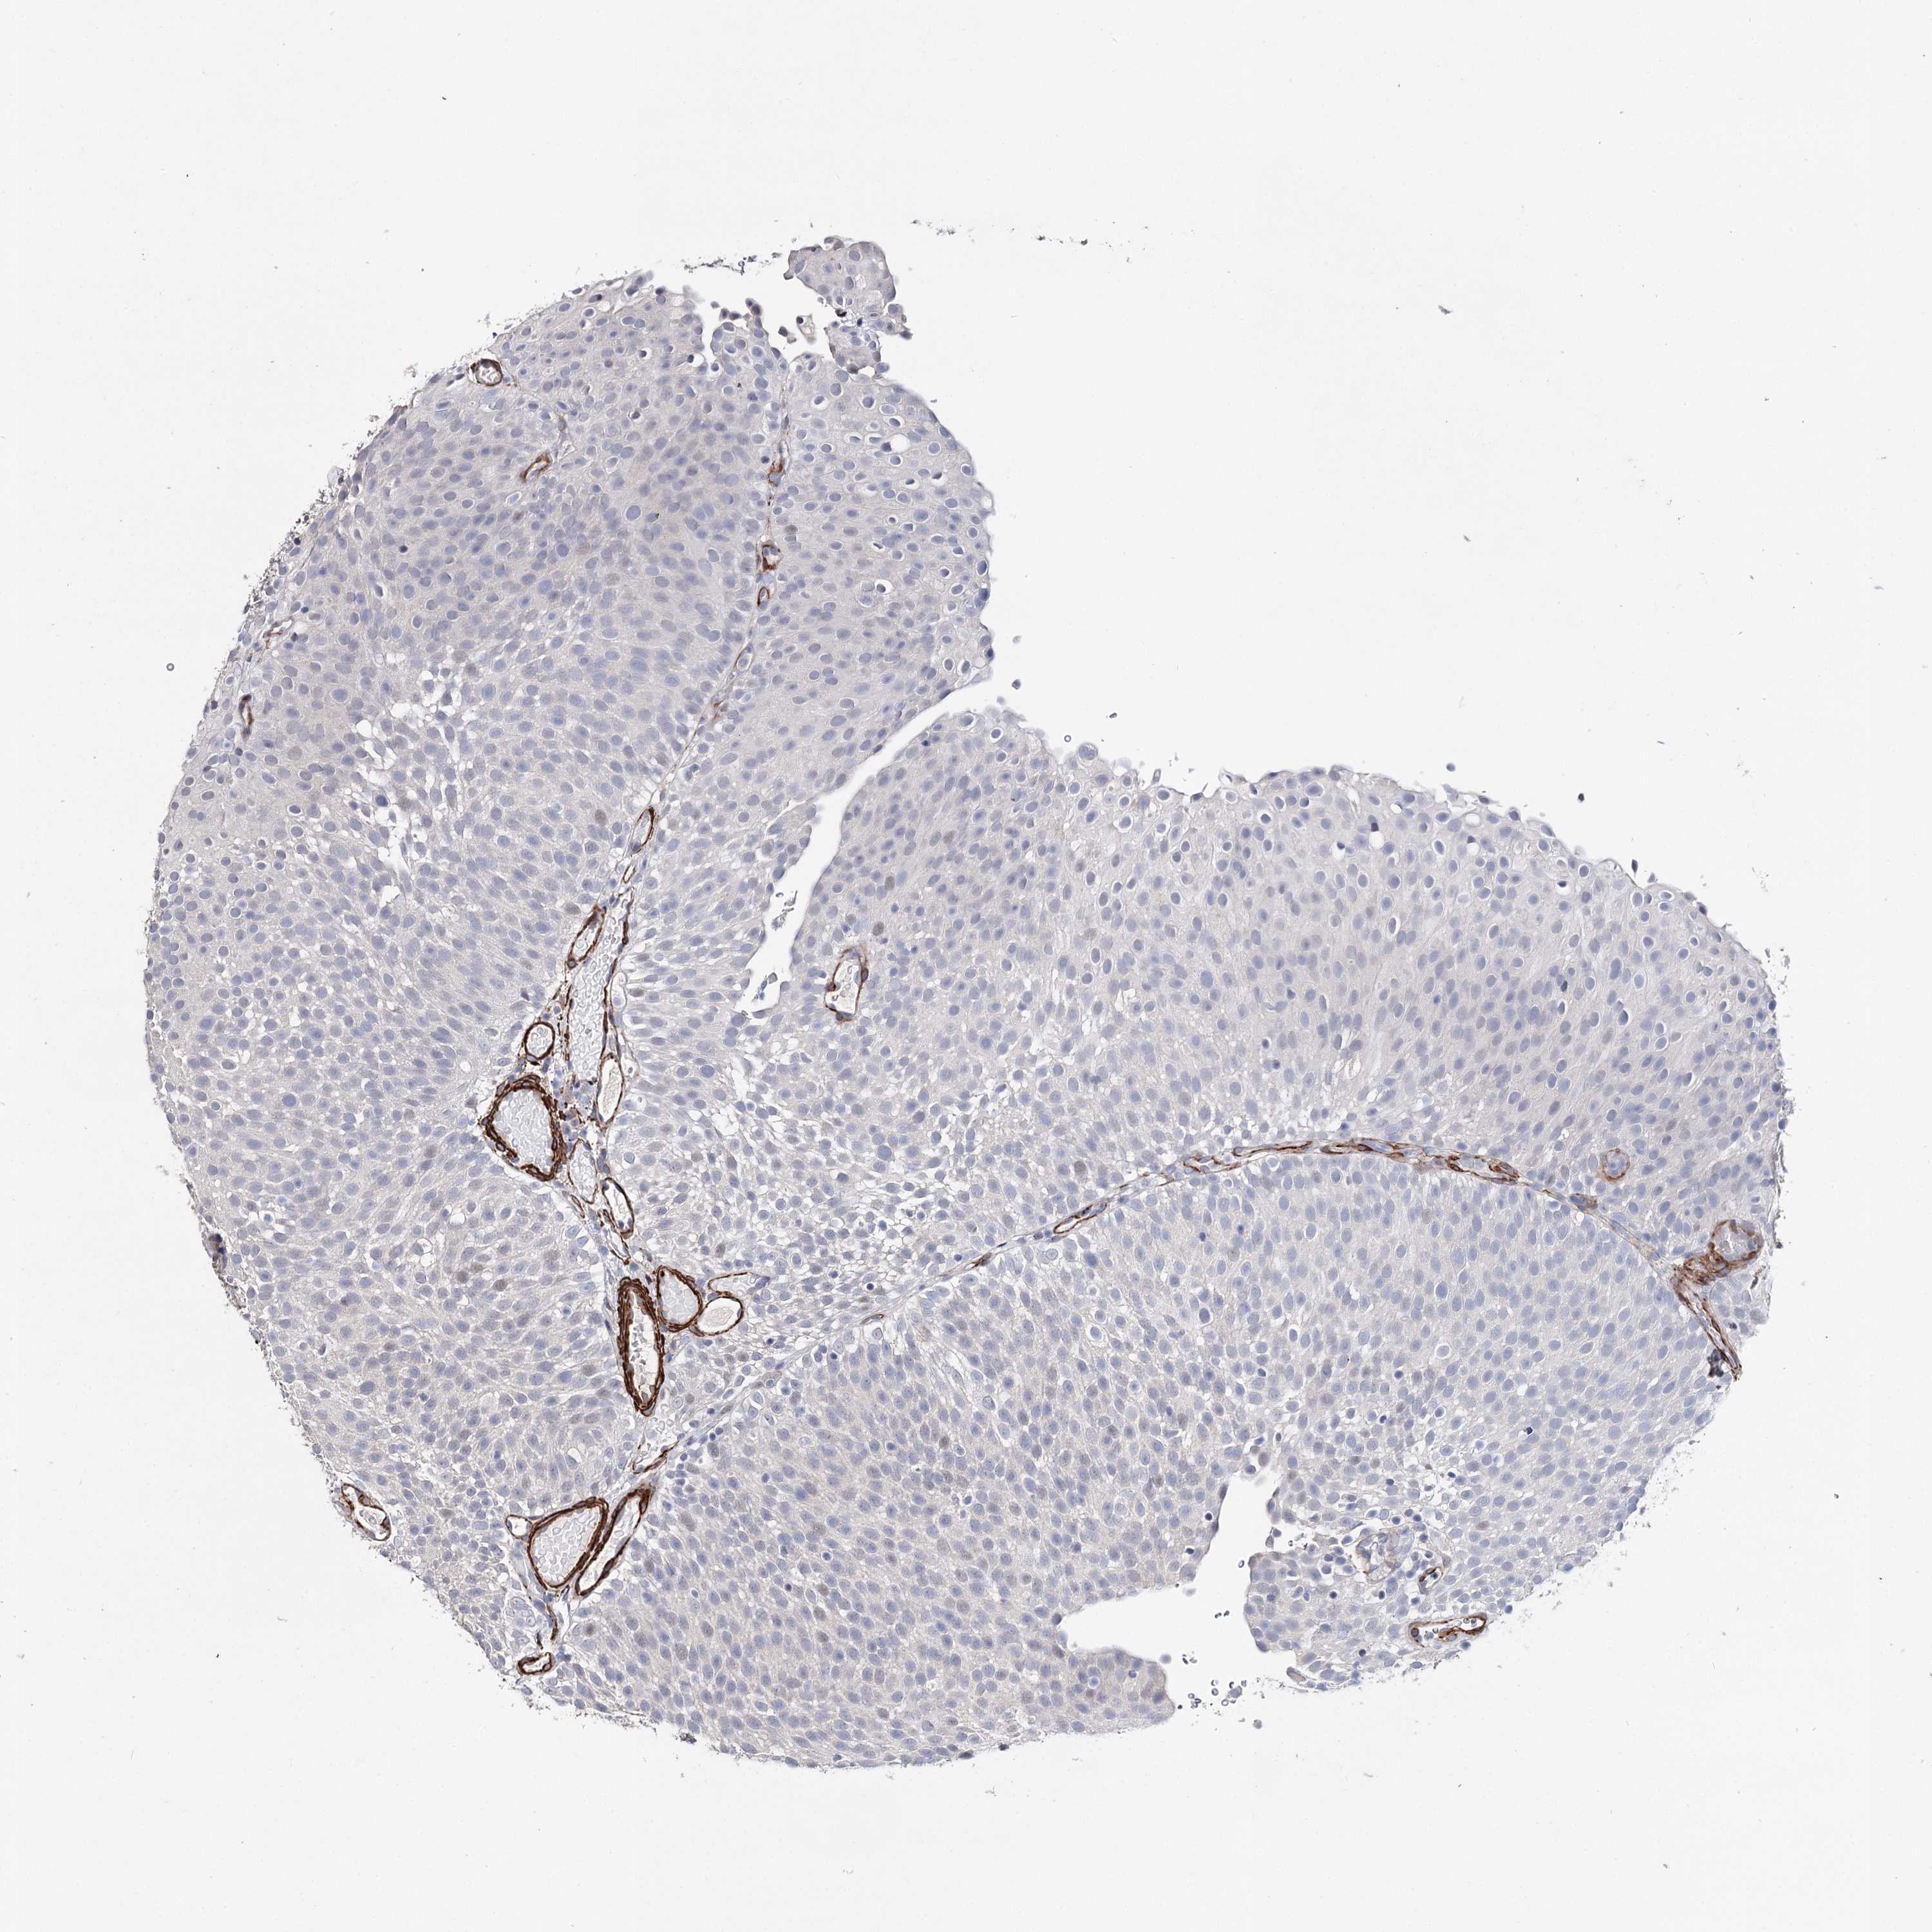

UROTHELIAL CANCER - Protein expressioni

A mouse-over function shows sample information and annotation data. Click on an image to view it in a full screen mode. Samples can be filtered based on level of antibody staining by selecting one or several of the following categories: high, medium, low and not detected. The assay and annotation is described here.

Note that samples used for immunohistochemistry by the Human Protein Atlas do not correspond to samples in the TCGA dataset.

Antibody stainingi

Antibody staining in the annotated cell types in the current human tissue is reported as not detected, low, medium, or high, based on conventional immunohistochemistry profiling in selected tissues. This score is based on the combination of the staining intensity and fraction of stained cells.

Each image is clickable and will lead to virtual microscopy that enables deeper exploration of all samples and also displays staining intensity scores, fraction scores and subcellular localization as well as patient and tissue information for each sample.

Antibody HPA037786

Antibody HPA038034

Antibody HPA038867

Antibody HPA038868

Urothelial carcinoma, High grade

Urothelial carcinoma, Low grade

Urothelial carcinoma, NOS